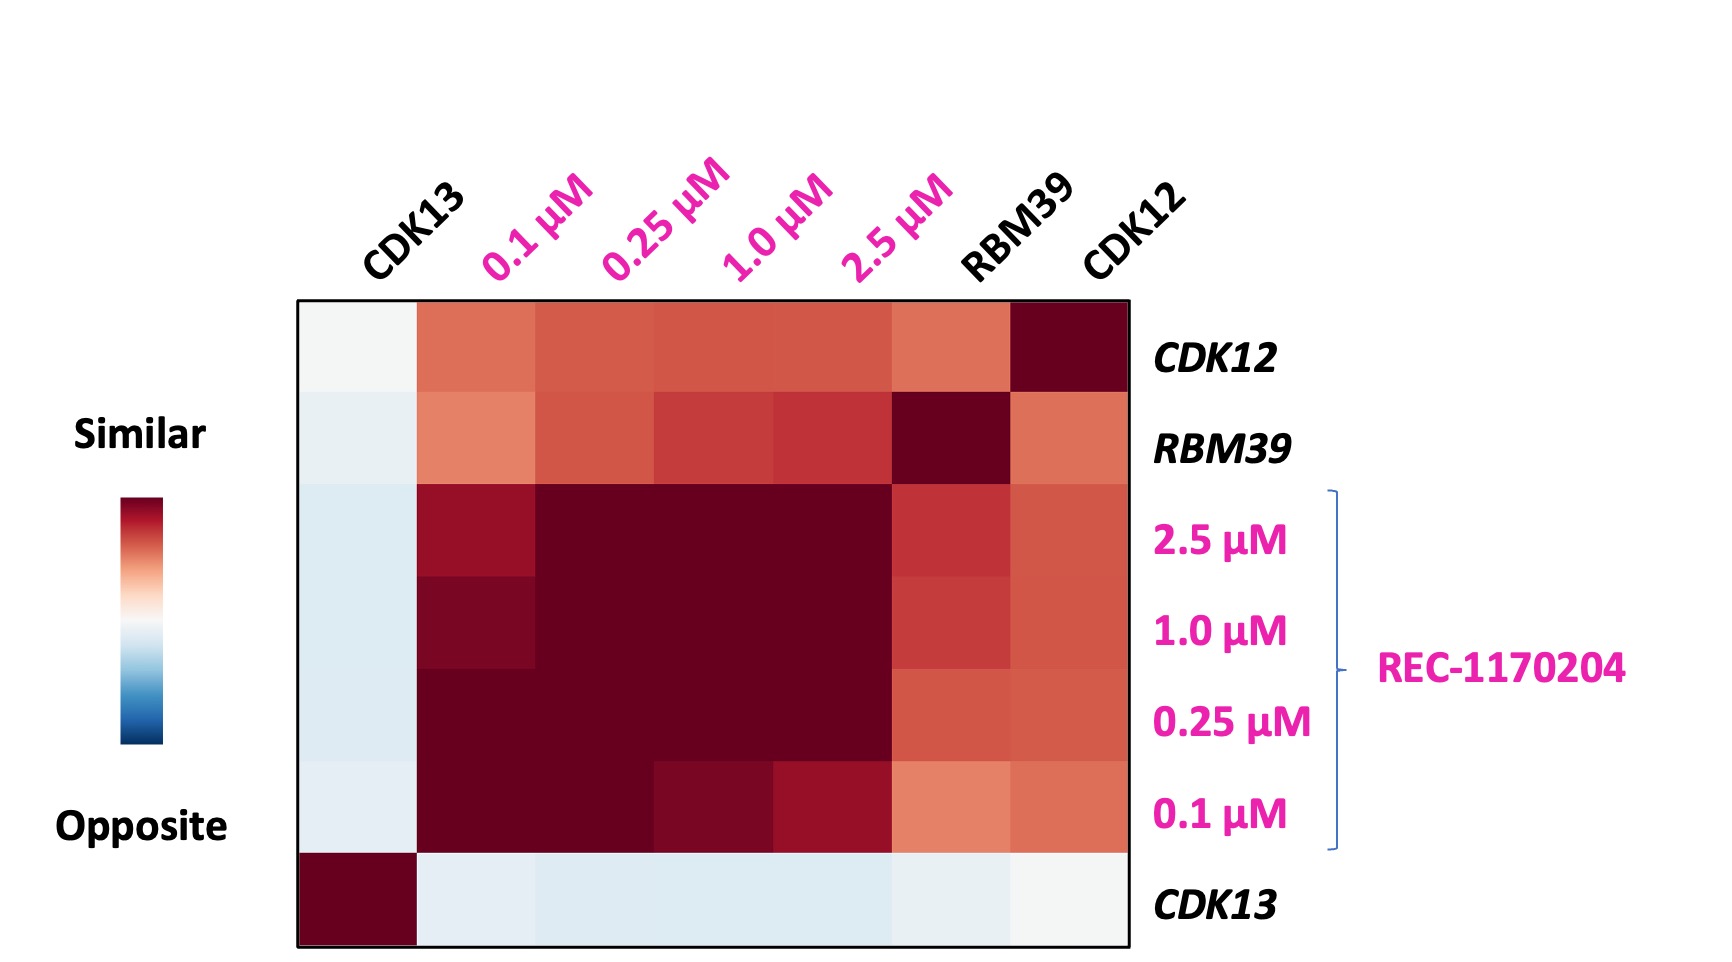

•Advanced our RBM39 program in homologous recombination proficient ovarian cancer and other solid tumors to IND-enabling studies